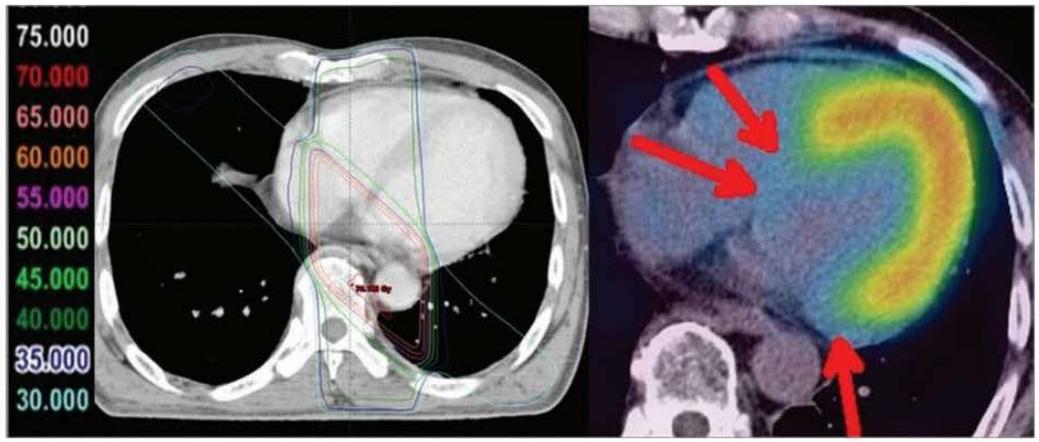

In 2013 Umezawa et al., demonstrated that external radiation therapy affected BMIPP uptake. The irradiated area of the heart (red arrows in Figure 4) showed no tracer uptake (143). Although the $\mathrm{CoQ}_{10}$ levels were not evaluated, the image pattern is highly suggestive of induced $\mathrm{CoQ}_{10}$ deficiency. In a subsequent publication the authors described a relation between the radiation dose applied and the degree of BMIPP alteration (144).

Fig. 3. Images of a remarkable case (62-year-old male) at 29 months after radiotherapy for esophageal cancer. Reduced uptake corresponding to radiation fields was distinct in this case.

Following the concept of metabolic switch from free fatty oxidation to glycolysis, Yan et al., have demonstrated that radiation-induced changes in myocardial metabolism are accompanied by a high uptake of $^{18}\mathrm{F}$ -FDG (Figures 2 and 3 in (145)), thus reflecting glycolysis.

Figure 4: Taken from Umezawa (143). The Figure is used on the basis of Creative Common CC-BY-NC. Umezawa R, Takase K, Jingu K, Takanami K, Ota H, Kaneta T, et al. Evaluation of Radiation-Induced Myocardial Damage Using Iodine-123 B-Methyl-Iodophenyl Pentadecanoic Acid Scintigraphy. J Radiat Res (2013) 54(5): 880-9. Epub 2013/02/16. doi: https://doi.org/10.1093/jrr/rrt011